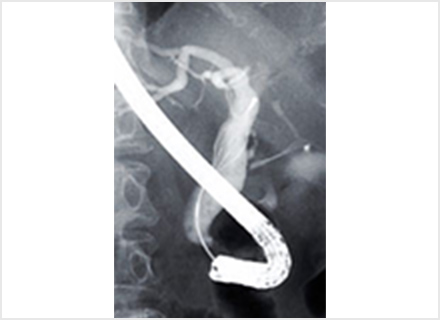

内視鏡的逆行性胆管膵管造影:ERCP(Endoscopic retrograde cholangiopancreatography)

内視鏡的逆行性胆管膵管造影(ERCP)は、十二指腸までスコープを進め、内視鏡の先端から造影カテーテルという細いチューブを膵管や胆管に挿入し、造影剤を直接注入してX線撮影を行います。 X線撮影だけではなく、管腔内超音波内視鏡(IDUS)を用いて胆管内を観察したり、顕微鏡で調べる組織を採取することも可能です。

また、内視鏡の先端から出したバスケット把持鉗子やバルーン付きカテーテルを用いて、胆管結石を砕いたり取り除いたり(採石)する治療や、腫瘍などで閉塞(狭窄)した胆管にステントを挿入し、胆汁の流れを良くする治療なども行っています。

管腔内超音波検査:IDUS(intraductal ultrasonography)

管腔内超音波検査(IDSU)は内視鏡の鉗子口から胆管や膵管に細長い管状の超音波を挿入し超音波画像を得る検査です。 細い胆管や膵管は腹部超音波検査や超音波内視鏡検査でも観察困難な場所ですが、内視鏡的逆行性膵胆管造影(ERCP)検査で細い超音波プローブを直接胆管や膵管に挿入することでより、詳細な画像情報を得ることが可能です。